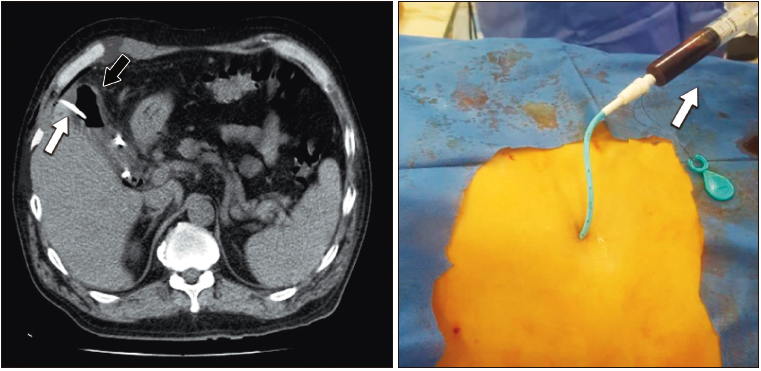

Hombre de 66 años, con antecedentes de tabaquismo, etilismo, diabetes mellitus tipo II, linfoma de Hodgkin diagnosticado hace 4 meses. El paciente estaba en el 12° día posterior a la quimioterapia. Fue derivado a nuestro centro por un dolor en hipocondrio derecho que irradia al dorso, fiebre y vómitos de 2 días de evolución. Durante el examen físico se encontraba en buen estado general y con signo de Murphy +. En los análisis se evidenció pancitopenia. La ecografía mostró la vesícula con engrosamiento mural y pequeña banda líquida circundante, y en su interior múltiples imágenes ecorrefringentes con sombra acústica posterior (litiasis) y otras sin sombra acústica posterior sugestivas de burbujas aéreas. Se decidió comenzar con piperacilina tazobactam como antibioticoterapia y realizar una TC, la cual informó vesícula con abundante contenido aéreo en su interior y paredes irregulares de aspecto enfisematoso; aerobilia y presencia de aire libre en espacio subperitoneal del hilio hepático. Realizamos una CP guiada por tomografía (Figura 5) con toma de cultivo. Al séptimo día posterior a la colecistostomía el paciente fue dado de alta sanatorial. Lo demás se realizó por ambulatorio.

Figura 5. Colecistostomía percutánea transhepática guiada por TC. Imagen de la

izquierda: se observa catéter en el interior de la vesícula biliar (flecha blanca). Presencia de aire en la

luz de la vesícula (flecha negra). Imagen de la derecha: catéter de 10 Fr. Se observa débito bilioso turbio

(flecha blanca)